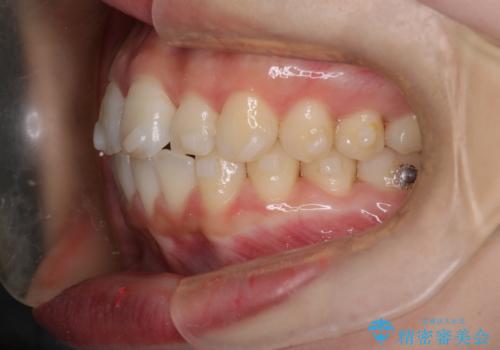

【インビザライン】前歯が出てるのを治したい

- 前歯の凸凹と前突を主訴に来院されました。

インビザラインにて治療をおこない、歯並びを改善することができました。